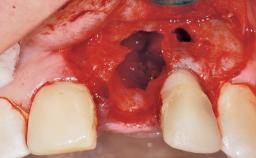

Late Flapless Placement of an Implant in a Maxillary Left Central Incisor Site

Anthony Sclar

A 39-year-old male patient presented with a chief complaint of discomfort and gingival discoloration around his maxillary left central incisor. He was in good general health and was a non-smoker. His past dental history was significant because of the traumatic fracture of tooth 21 in a sporting accident at age 13. Initial dental treatment included endodontic therapy and a full-coverage restoration. The patient became symptomatic 5 years later, when structural failure of the tooth resulted in the dislodgment of the crown. Endodontic retreatment, apical surgery, and post-and-core restoration were performed.